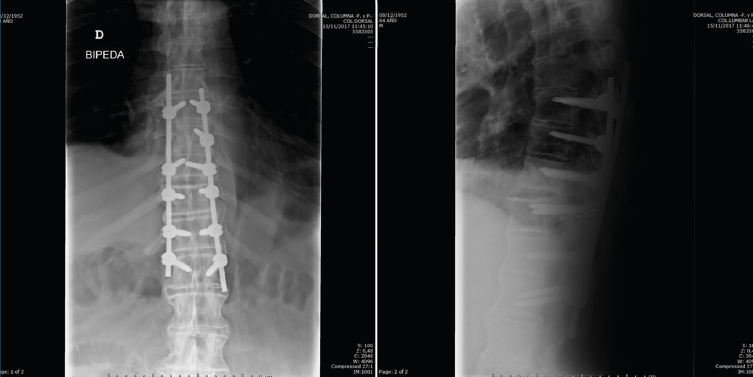

Figura 7. Control a los 2 meses de la cirugía.

Se realizó un control a los 2 meses de la cirugía, previo al inicio de rehabilitación (Figura 7).

Figura 8. Control final a los 5 meses de la cirugía.

En la Figura 8 vemos el control final a los 5 meses de la cirugía.